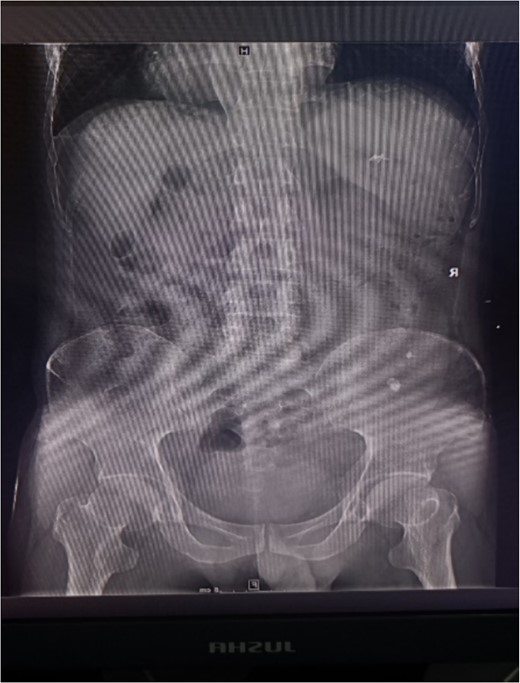

Abdominal CT showing multiple punctate stones in the right renal area in situ.

A 39-year-old man with kidney stones after kidney transplantation was admitted to our hospital on 29 November 2023. Eight years ago, he underwent a kidney transplant from a donor. Neither the donor nor the recipient had a history of kidney stones. The transplanted kidney was positioned in the right iliac fossa, and the patient had a successful postoperative recovery. However, a recent routine abdominal computed tomography (CT) scan revealed multiple stones in the transplanted kidney and bilateral in situ kidney atrophy. The stone was located in the lower calyx of the transplanted kidneys. Hydronephrosis was also observed. Kidney, ureter, and bladder radiographs showed multiple high-density speckles in the right kidney, the largest of which was ~0.5 cm in diameter. Physical examination (blood pressure, 147/91 mmHg; serum creatinine, 72.7 μmol/L; urea nitrogen, 5.1 mmol/L) revealed normal liver function, coagulation, and electrolytes. We suspected that these kidney stones were sizable and necessitated surgical intervention. Upon admission, pertinent examinations were conducted, and preoperative preparations were completed.